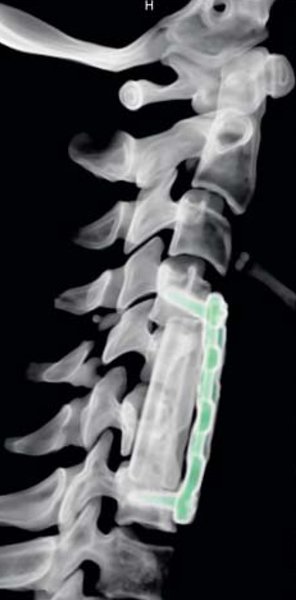

Eine Umfrage unter führenden Industrieunternehmen der Medizintechnik und Kliniken ergab eine durchweg positive Bewertung des neuen Studiengangs. Das Master-Studium Medizintechnik vermittelt die Fähigkeit, in international tätigen Unternehmen mit Forschung, Entwicklung, Produktion und Service in der Medizintechnik Aufgaben mit Führungsverantwortung in verschiedenen Tätigkeitsbereichen zu übernehmen. Zu diesen zählen etwa Entwicklungs- und Innovationsmanagement, Systementwicklung und Medizintechnikmanagement, IT- und bildgebende Verfahren, Entwicklung und Forschung in der Medizintechnik, simulationsbasierte Entwicklungsprozesse, Diagnostik, Prozess- und Qualitätsmanagement. Die Absolventinnen und Absolventen sind damit in der Lage, eine herausgehobene berufliche Verantwortung zu übernehmen, komplexe Aufgabenstellungen zu leiten und die fachliche Entwicklung von Teammitgliedern gezielt zu fördern. Zudem erstreckt sich die Qualifikation im Master Medizintechnik auf anwendungs- oder forschungsorientierte Aufgaben und Projekte.